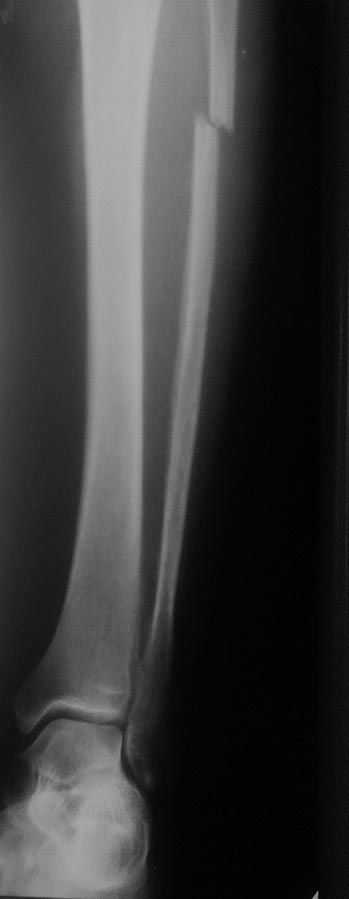

Очевидно, что это перелом не 44С. Механизм травмы - прямой удар. Это косой перелом м/берцовой кости без повреждения голеностопного сустава и межкостный мембраной, которые наблюдаются при переломах 44С. При этом дисторсия связок г/ст сустав возможна как отдельное повреждение, с другим межанизмом, которое последовало вслед за переломом в результате непрямого воздействия. Такой перелом не нуждается ни во внутренней фикции, ни во внешней иммобилизации. Как лечить дисторсию тоже знаете.

Смущает одно, что при наружной ротации стопы боль передаётся на область перелома малоберцовой кости в верхней/3 и болезненность в проекции дельтовидной связки, и линия перелома м/берцовой кости косая (ближе к спирали).

По рентгенологической картине это перелом от сгибания, а не от скручивания, что бывает при 44С3.